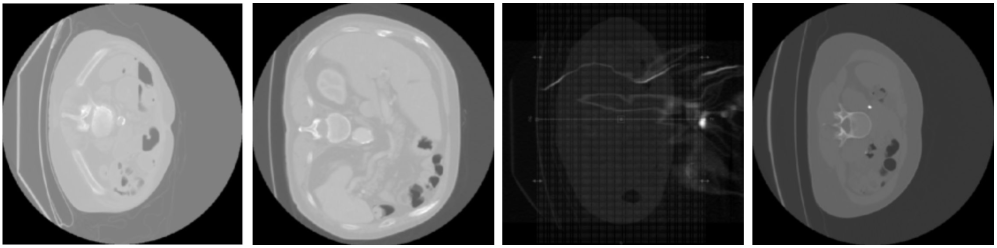

As this paper focuses on learning image representations from brain MRIs, we had to ensure that all report content was visually grounded in the corresponding images. For example, keyword filtering revealed that 94% of reports make references to prior scans. Figure 9 contains an example report showing the two main types of information not detectable from the image: references to prior scans and description of findings not visible on T1 post-contrast images.